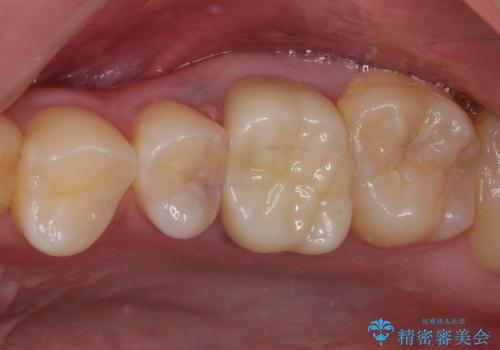

途中来院されない時期があったため、初診から終了まで期間がかかりましたが、根管治療を行った歯の根尖病変はいずれも改善を確認することができました。

口腔内の金属が全てなくなり、患者様には大変満足していただきました。